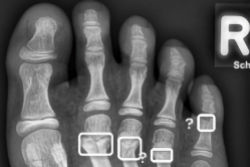

- Pretraining AI models on adult chest x-rays improved performance when the model was refined with pediatric data.

- Lateral x-rays provided complementary information -- which was "especially valuable in infants and young children, where the frontal view alone may be insufficient," the investigators noted.

- The study showed that age-specific models were preferred "over models trained across all ages, due to differences in disease presentation and developmental stages among age groups," they wrote.